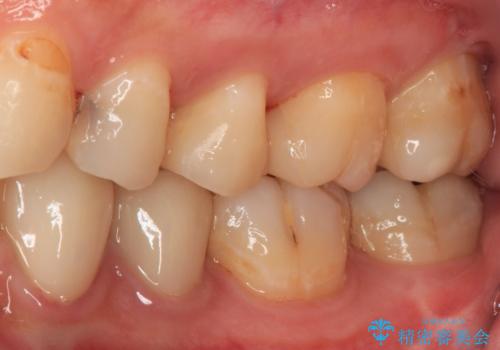

精度の高いセラミックインレーによる修復治療を行うこととしました。

処置を行った歯以外にもむし歯と思われる歯が多数ありますが、費用のかかる治療であれば、優先順位をつけて、処置を急ぐ歯から処置を進めて行きました。